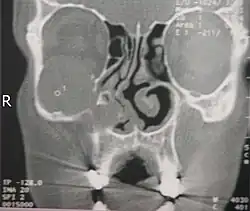

![]() TK śuzowiaka prawej zatoki szczękowej, powodującego wybrzuszenie wyrostka haczykowatego kości sitowej | |

Diagnostyka jedynie radiologiczna. Daje to obraz zakresu ekspansji śluzowiaka, jej położenie, stosunki anatomiczne z innymi strukturami, co jest kluczowe dla zaplanowania leczenia operacyjnego na oddziale otolaryngologicznym. Podstawowym badaniem jest TK zatok przynosowych w kilku projekcjach. Wartość diagnostyczna zwykłego zdjęcia rentgenowskiego zatok przynosowych jest oceniana jako raczej znikoma. Badanie MRI pokazujące bardzo dobrze tkanki miękkie uzupełnia jedynie badanie TK, gdyż nie widać na nim kości, co jest ważne dla określenia np. zniszczenia kości przez śluzowiaka.